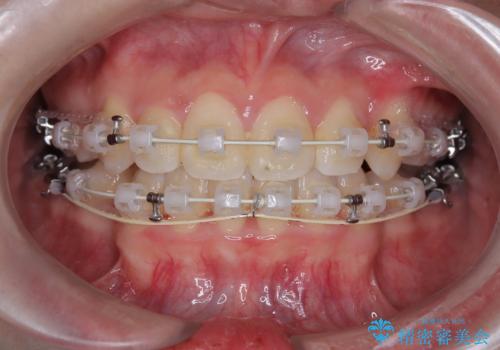

【埋伏歯】犬歯の牽引を行った矯正歯科治療

- 矯正装置

左側犬歯が埋伏していましたが、第一小臼歯(4番目の歯)を抜歯したことでできたスペースに牽引し、右側の飛び出した八重歯を含め、歯全体を整列することができ患者様も満足していただきました。